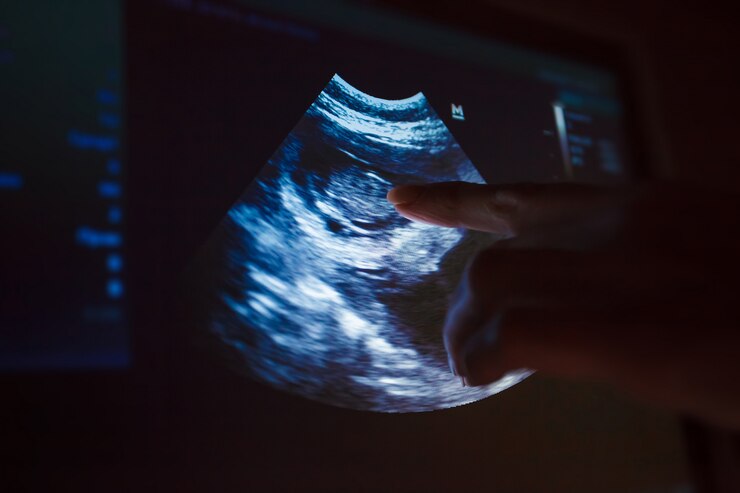

Vision Veterinary Imaging provides an innovative Pregnancy Check service that uses the latest advanced technology and offers same-day service for pets in Palm Beach County and its surroundings.

By checking the levels of the hormone relaxin, a blood test can identify pregnancy in a pregnant dog. This hormone can be found in the blood of the majority of pregnant females as early as 22–27 days after conception.